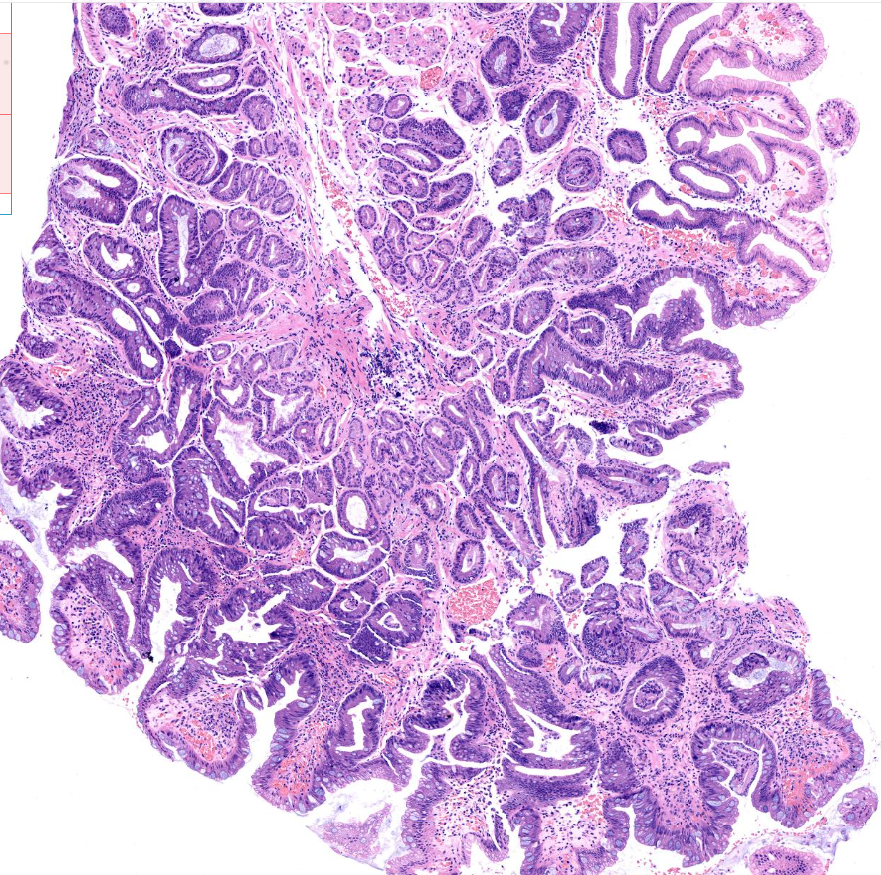

胃体息肉?

性别

男

年龄

32岁

临床诊断

一般病史

体检

标本名称

胃体

大体所见

胃体息肉样隆起0.6*0.5cm,活检1块

萎缩肠化部分区域腺体考虑为低级别上皮内瘤变,会不会是低级别管状腺瘤

增生性息肉伴肠化

考虑增生性息肉,伴肠化。